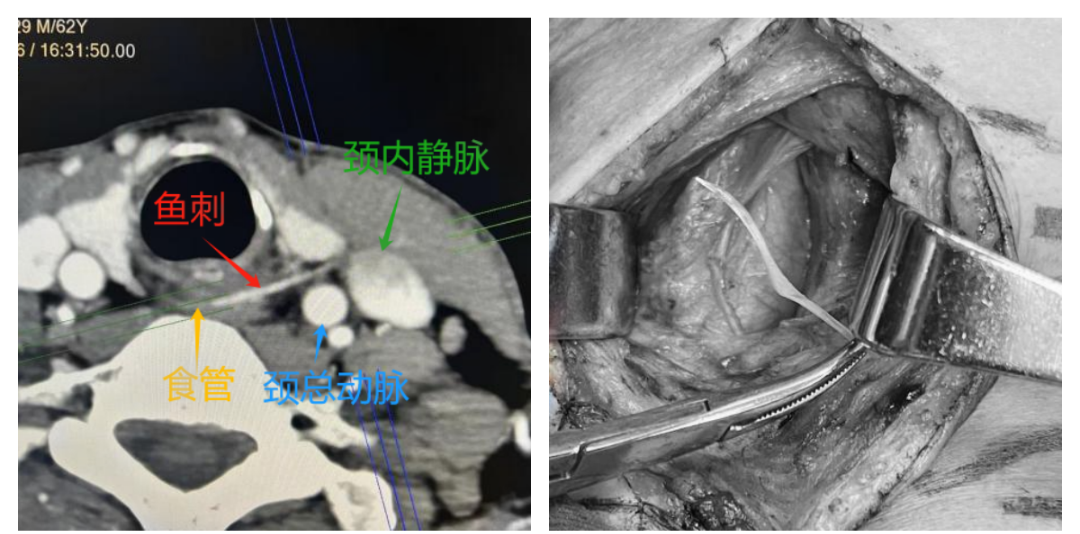

任子涵医生接诊查体后,并未在咽喉部看见明确鱼刺。然而患者痛苦的表情让他立刻警觉起来。颈部CT及三维重建检查图像清晰显示:一根长近3cm的尖锐鱼刺,已完全穿透食管壁,滞留于颈深部软组织内,且尖端像一把利剑已经刺入颈动脉鞘,与颈内静脉紧紧相贴。病情危急,颈内静脉及颈总动脉为头颈部核心大血管,一旦被鱼刺刺破,将引发致命性大出血,短时间内可致失血性休克,且轻微的吞咽、转头等动作,均可能加重鱼刺对血管的损伤,诱发严重并发症。

全麻下,术者探查发现鱼刺尖端紧紧抵住颈部大血管,与术前研判完全一致。团队沉着应对、精准把控,每一步操作均做到分毫无差,避免对血管及周围组织造成二次损伤。最终,术者凭借精湛的外科技术,将这根“致命鱼刺”完整钳夹取出,手术过程顺利,未出现任何术中并发症。术后患者安返病房,生命体征平稳。